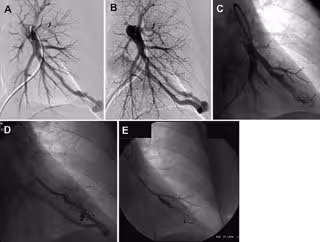

Este procedimiento consiste en pasar un catéter desde un vaso sanguíneo grande de la pierna hasta el punto donde se encuentra la malformación. A continuación se inserta una pequeña bobina para bloquear la PAVM. El procedimiento es altamente efectivo, pero las MAP persistirán en algunos pacientes.

Para el nuevo estudio, el doctor Misra y sus colegas querían ver cómo fumar podría afectar las tasas de persistencia de las MAP tras la embolización. Observaron a 103 pacientes con THH que se sometieron a embolización por un total de 373 MAP. Los pacientes fueron clasificados en grupos de fumadores o no fumadores.